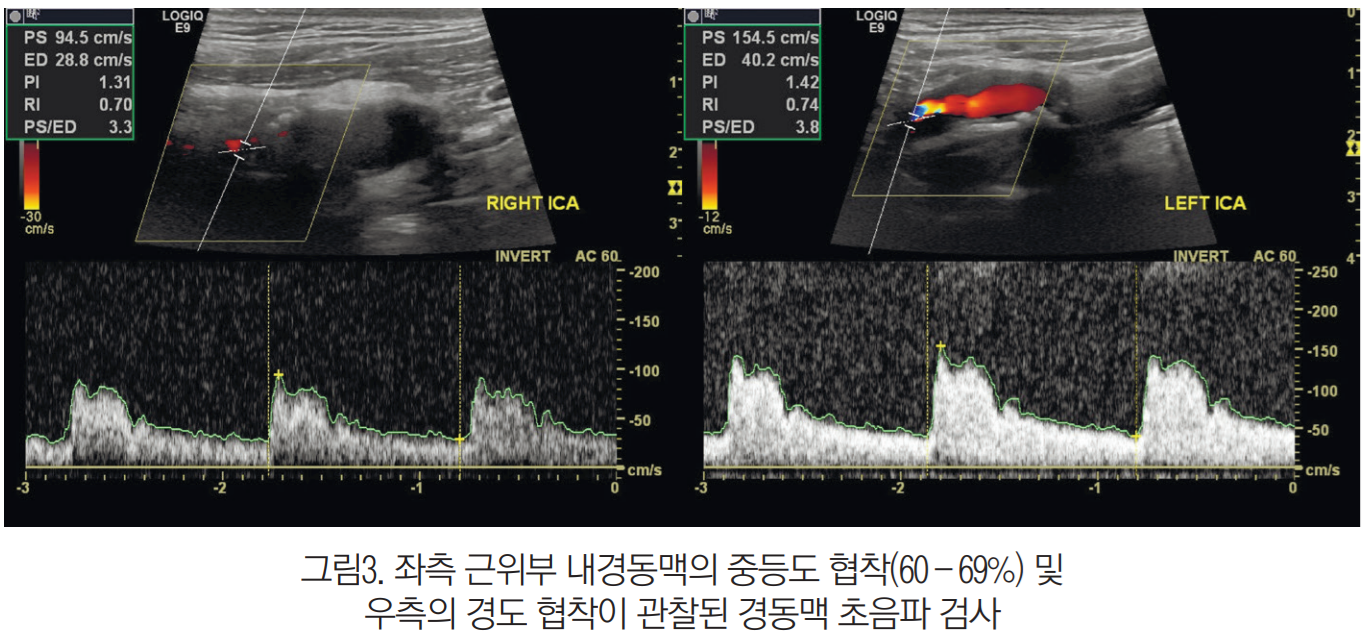

환자에게 아버지의 뇌경색과 관련된 초진 기록, 영상의학적 검사 자료 및 최근 진료 기록 등 의무기록사본을 발급받아 오시도록 했다. 기록을 확인해 보니 환자의 아버지는 좌측 안쪽 연수 뇌경색이었고, 혈관조영검사상 좌측 척추동맥 및 양측 내경동맥에 협착이 있었다.

그리고 좌측 대퇴골 전자간부 골절로 경피적 골수강외 정복술 및 골수내 정 고정술을 받았다(그림2). 경동맥 초음파 검사에서는 좌측 근위부 내경동맥에서 중등도 협착, 우측에서는 경도 협착이 확인됐다(그림3).